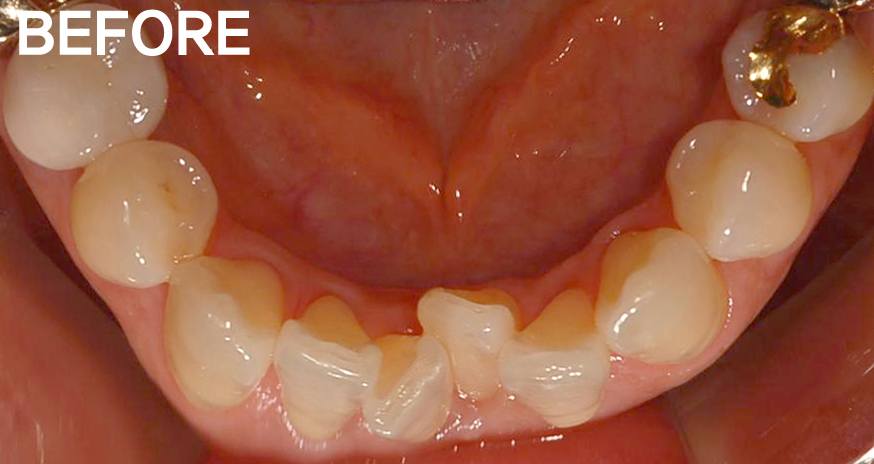

궁금한 내용은 아랫 앞니부분이 부분교정이 가능한지 궁금하신것 같습니다.

앞니가 삐뚤하기 때문에 치아표면에 착색이 되어 충치처럼 보입니다.(착색이지 충치는 아닙니다. 치아를 교정하면 치솔질이 용이하기때문에 착색이 생기는것도

교정기간은 5개월전후면 충분히 가능하고 비용은 150만원(월교정비는 4만원)입니다.